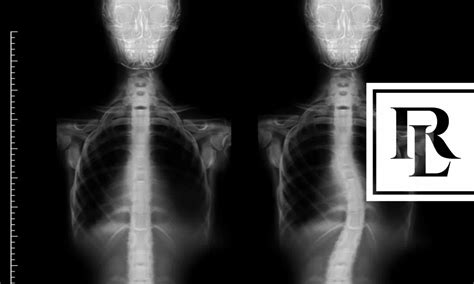

Alright, so first things first: what exactly is scoliosis ? Simply put, it’s a condition where the spine curves to the side. While some folks might have a mild curve that they barely notice, others can experience more significant curvature that messes with their lives in a big way. The causes can vary – sometimes it’s there from birth, other times it develops during the teen years, and in some cases, it’s due to other medical issues. Symptoms can range from barely-there to pretty intense, including back pain, uneven shoulders or hips, and even breathing problems if the curve gets severe enough.

Furthermore, the severity of scoliosis plays a crucial role in the impact it has on an individual’s life. Mild scoliosis , often involving curves less than 25 degrees, might not cause significant problems, and individuals may manage it with observation, exercise, or physical therapy. However, moderate scoliosis , typically with curves between 25 and 40 degrees, could start to cause noticeable symptoms like back pain, fatigue, and posture changes. This can make certain activities difficult or uncomfortable. Severe scoliosis , which involves curves greater than 40 degrees, can lead to serious complications. Breathing difficulties can occur as the rib cage is affected, and chronic pain and mobility limitations become more pronounced. This level of severity can drastically impair one’s ability to perform daily tasks and maintain employment. The type and location of the curve also influence the impact. Thoracic curves (in the upper back) might affect breathing more, while lumbar curves (in the lower back) can cause more issues with mobility. All these aspects highlight why understanding the specific characteristics of an individual’s scoliosis is vital in assessing its impact and the need for support.

Getting a proper diagnosis is the first step. Doctors typically use X-rays to measure the curve of the spine. From there, the course of treatment depends on the severity of the curve and other factors. Treatment options can include observation (for mild cases), bracing to prevent the curve from getting worse, physical therapy to improve strength and flexibility, and, in severe cases, surgery to correct the curve. Managing scoliosis effectively can make a huge difference in the lives of those affected, helping to ease pain, improve mobility, and maintain a higher quality of life. Regular check-ups are super important to monitor the progression of the curve and adjust treatment as needed. Remember, early intervention and the right kind of care can go a long way in managing scoliosis and its impact.

To be eligible for disability benefits, you typically need to demonstrate that your scoliosis causes significant functional limitations. The SSA assesses your ability to perform basic work-related activities. This includes things like sitting, standing, walking, lifting, and carrying. If your scoliosis makes it difficult or impossible to perform these activities, you might be considered disabled. Medical evidence is crucial for proving your case. This includes X-rays showing the curve of your spine, doctor’s notes, treatment records, and any reports from specialists. The SSA will also consider the impact of your scoliosis on your ability to work, taking into account your age, education, and past work experience. This might sound complicated, but understanding the criteria is the first step in getting the support you need. The SSA’s decision is based on a comprehensive assessment of your medical condition and its effect on your ability to work.

Medical records are the foundation of your claim. Make sure to collect all the relevant documents. This includes X-rays, MRI scans, and any reports from specialists. These records will help to demonstrate the severity of your scoliosis. Doctor’s notes are equally important, as they provide a narrative of your condition, treatment, and progress over time. These notes should include details about your symptoms, physical examinations, and any treatments you have received. If you’ve undergone surgery or other procedures, make sure to include the operative reports and any post-operative notes. Also, include any notes from physical therapy, occupational therapy, or any other rehabilitative services.